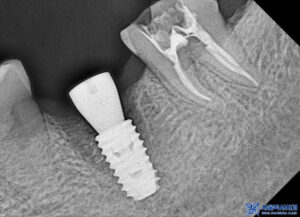

발치 전 CT를 촬영하여

잇몸과 치아 주위의 뼈 상태를

정밀히 파악한 후,

발치가 필요한 치아와 그 주변 구조에 대한

상세한 정보를 얻을 수 있었습니다.

이를 바탕으로 발치 후 임플란트를

식립할 위치와 각도를 정밀하게

계획하였습니다.

이후 무절개임플란트를

진행하였습니다.

본원에서는 무절개로 임플란트를

진행하고 있으며,

컴퓨터 분석을 통해 미리 식립 위치를

시뮬레이션하여 식립 오차를 줄이며,

부기가 많이 없고 회복이

빠른 장점이 있습니다.